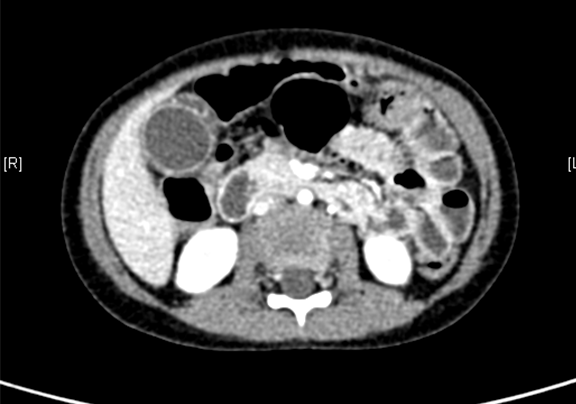

术前CT检查:

动脉期

上腹部增强CT:1. 胆总管囊肿、肝内胆管略扩张2. 胆囊壁厚,考虑胆囊炎可能性大。